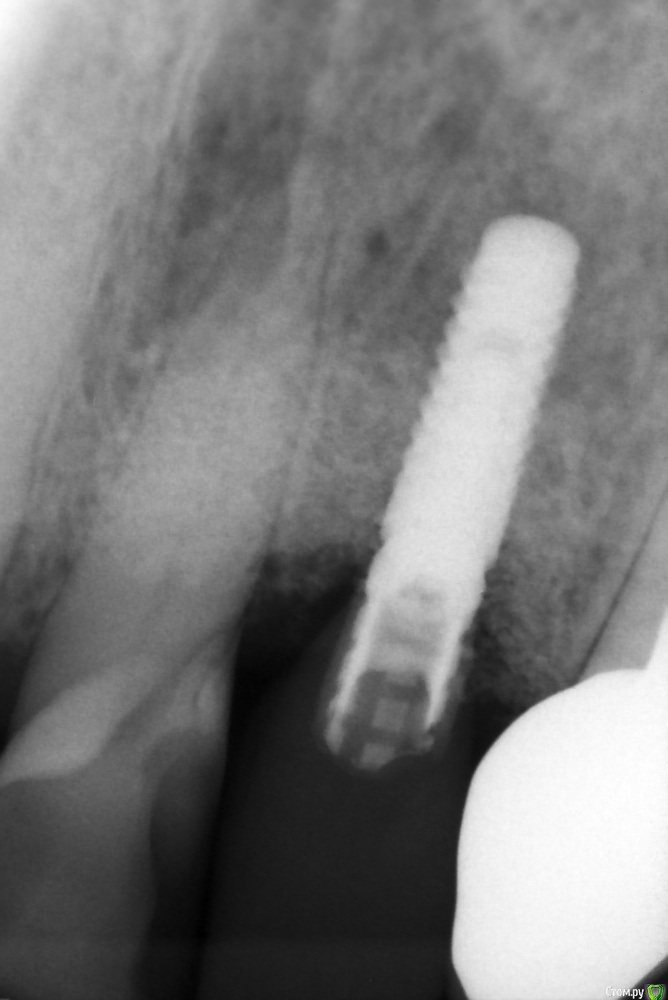

andr99 Опубликовано 13 марта, 2016 Поделиться Опубликовано 13 марта, 2016 (изменено) Имплантат не мой. Пациент пришёл ко мне уже вот так. Ранее была проведена нкр +имплантация не очень удачно - винт потеряли. Повторная имплантация с пластинкой десны (вроде как vip-ct) тоже, как видно, не особо здорово.От удаления винта и "все по новой" категорически отказался.http://s019.radikal.ru/i640/1603/31/e82f0fc87237.jpgСитуация после пластики сст с бугра и года ношения коронкиhttp://s020.radikal.ru/i709/1603/40/55a1fb73f3ab.jpg Изменено 13 марта, 2016 пользователем andr99 19 Ссылка на комментарий

kriokov Опубликовано 13 марта, 2016 Поделиться Опубликовано 13 марта, 2016 andr99что могло выросло, штрауманн нормально стоит. У меня такое впечатление сложилось, что там все проблемы из за голого корня 21, реставрация там так себе, выше эмалецем границы похоже все контаминировано. 2 Ссылка на комментарий

andr99 Опубликовано 14 марта, 2016 Автор Поделиться Опубликовано 14 марта, 2016 Будете предпринимать попытку добавить ещё тканей? Пациент не горит желанием(( ему и так все нравитсяandr99что могло выросло, штрауманн нормально стоит. У меня такое впечатление сложилось, что там все проблемы из за голого корня 21, реставрация там так себе, выше эмалецем границы похоже все контаминировано. Вот и у меня возникло подозрение, что все бы и так выросло)))Реставрацию, на сколько помню, делали уже по факту.. 1 Ссылка на комментарий